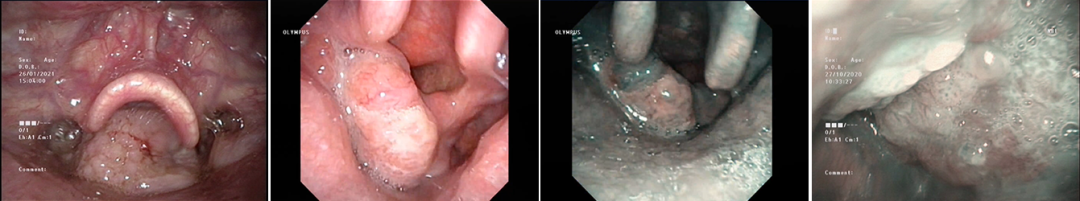

电子喉镜显示:左侧梨状窝内侧壁肿物,累计梨状窝尖。

980nm Diode光纤原本的认识只在耳硬化症手术的激光镫骨底板“一枪成型”术上呈现出“快、准、简、好”等革命性优势。

如今应用到下咽病损肿物切除上,体验感觉并不是单纯对CO2激光的性能补充,而是拥有另外一种功能特性的激光刀的应用。与CO2激光光纤在血供丰富区域切割相比,不会因为出血而导致切不动,而且可弯曲角度更大,最小弯曲半径达到36mm,很好地在角度内镜配合下清除藏匿在较深部位的病损;0.3mm的刀头直径,切缘及安全缘的选择判断更加准确安全;可以配合不同光纤器械对或深或浅的腔内不同部位病损肿物进行精准切除,而且术后黏膜上皮恢复更好更快。